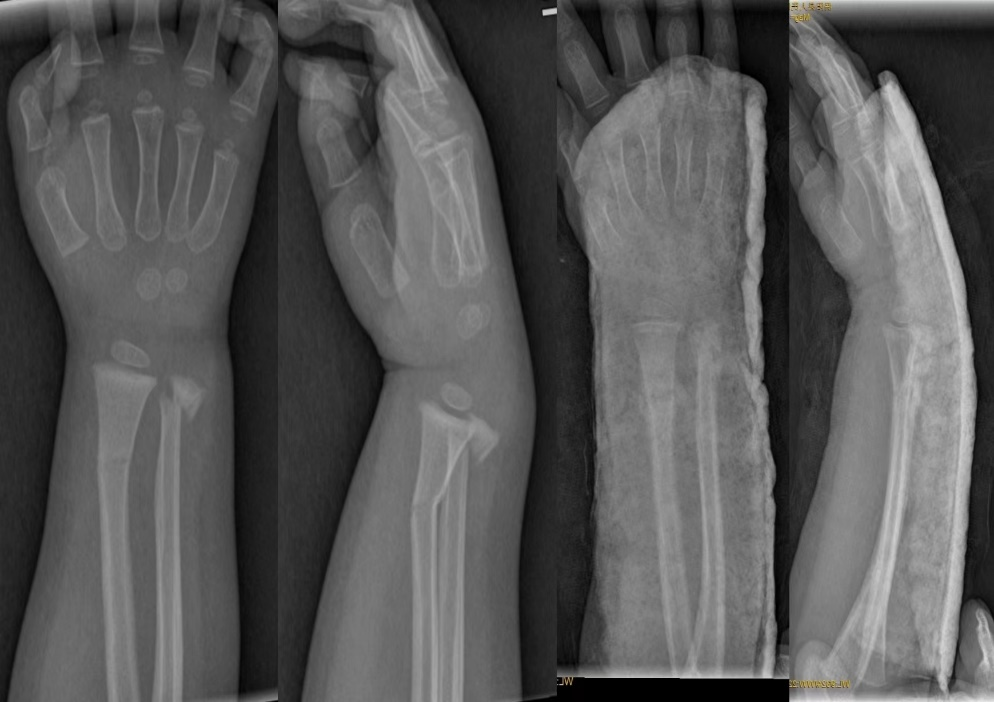

桡骨远端骨折(Distal radial fractures)---是指距桡骨远端关节面3cm以内的骨折,是松质骨和密质骨的交界处,横截面呈四边形且骨皮质较弱因此力学结构较弱,骨折后容易发生松质骨的塌陷,皮质骨的粉碎及桡骨缩短现象。

Colles骨折:最多见于跌伤:手臂伸出,前臂旋前,腕背伸,以手掌着地。

Smith骨折:此类骨折多为跌倒,腕背着地,腕关节急骤掌曲致伤。或跌倒时手掌伸展,旋后位着地而造成。即患者向后跌倒,上肢伸直且手掌面着地,向掌侧移位。

Barton骨折 桡骨远端关节面纵斜型骨折,伴腕关节脱位或半脱位。

1.手法复位石膏支具固定:对于简单、稳定的关节外骨折及部分关节内骨折,通常手法复位石膏或夹板同定即可获得较为满意的疗效。石膏外固定可以控制对位,但不能对抗轴向负荷,60%的复位丢失发生于1周内,因此,应在术后1周开始摄片复查。在复查随访中除了监测复位情况外,还要注意观察有无其他并发症发生。常见的并发症有皮肤压疮、骨筋膜室综合征、反射性交感神经营养不良、骨量丢失加速、关节僵硬等。